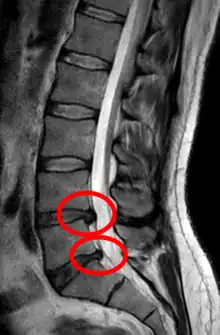

Herniated lumbar disc

Lumbar disc herniations occur in the back, most often between the fourth and fifth lumbar vertebral bodies or between the fifth and the sacrum. Here, symptoms can be felt in the lower back, buttocks, thigh, anal/genital region (via the perineal nerve), and may radiate into the foot and/or toe. The sciatic nerve is the most commonly affected nerve, causing symptoms of sciatica. The femoral nerve can also be affected and cause the patient to experience a numb, tingling feeling throughout one or both legs and even feet or a burning feeling in the hips and legs.[22] A herniation in the lumbar region often compresses the nerve root exiting at the level below the disc. Thus, a herniation of the L4–5 disc compresses the L5 nerve root, only if the herniation is posterolateral.

Click images to see larger versions